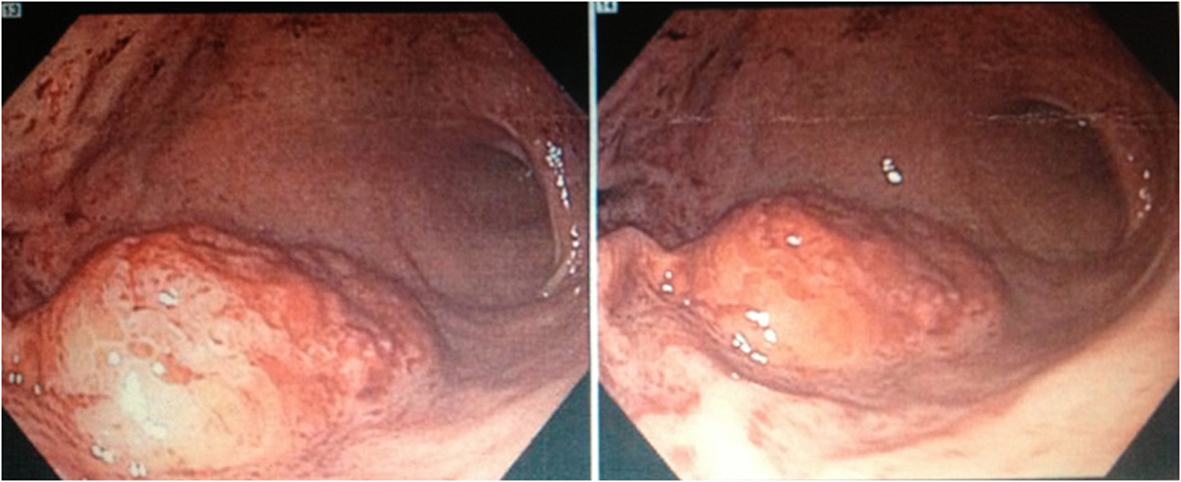

An esophagogastroduodenoscopy (EGD) was performed which revealed a large gastric antral mass that was biopsied (Fig. 1) as well as multiple bleeding Dieulafoy lesions in the gastric fundus that were subsequently hemoclipped. The biopsy report showed clusters of large, monomorphic, malignant lymphoid cells with 1). positive staining for CD3, CD4, CD8, and MUM-1; 2). a high proliferation rate (95%) by Ki-67; and 3). negative staining for CD10, CD20, CD30, CD56, EBER, ALK-1, and TIA-1. These findings were consistent with peripheral T-cell lymphoma but excluded the diagnosis of ALK-1 positive and negative anaplastic large cell lymphoma, extranodal NK/T-cell lymphoma, and cytotoxic T-cell lymphoma. A staging CT scan showed an approximately 2 × 1.9 cm soft-tissue mass inseparable from the right psoas but without any significant mediastinal, hilar, or axillary lymphadenopathy. The remainder of his staging work-up including bone marrow biopsy, CSF, and further imaging would return negative for involvement by lymphoma.

![]() Click for large image | Figure 1. Esophagogastroduodenoscopy (EGD) revealing a large mass located in the gastric antrum with biopsy later showing the presence of clusters of malignant lymphoid cells with staining characteristics consistent with peripheral T-cell lymphoma. |